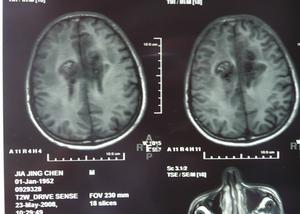

額葉腫瘤CT圖3.錐體束損害症狀額葉腫瘤時病灶對側腹壁和提睪反射的減弱消失以及同時出現強直性跖屈反射,常為早期症狀,隨著腫瘤的繼續增大及對運動區的侵犯程度病灶對側可出現肌張力增高,腱反射亢進,同時往往伴有踝陣攣、臏陣攣和腕陣攣等,最後可出現病灶對側的不同程度的癱瘓,Babinski征是皮質脊髓束病變的一種有代表性的重要體徵,額葉皮質運動區任何部位的腫瘤都可以出現。

額葉腫瘤CT圖主要特點如下:

(1)額葉底部腫瘤、(2)額極腫瘤、(3)額葉矢狀竇旁腫瘤、(4)額葉下部腫瘤。